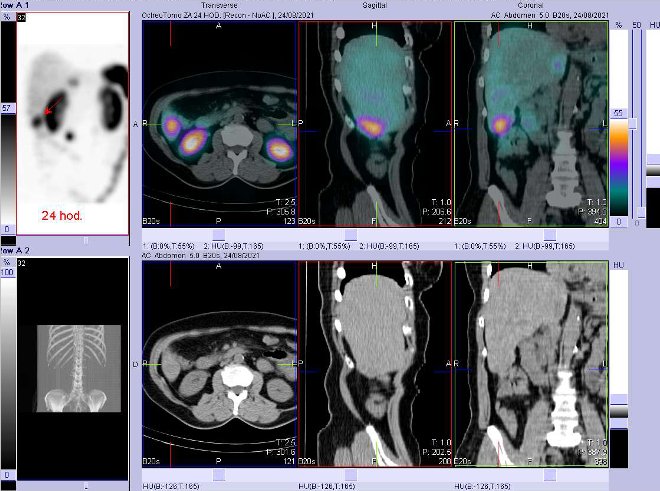

/ Obr. č. 7: Fúze SPECT/CT 24 hod. po aplikaci OctreoScanu. Zaměřeno na ložisko na rozhraní pravého a levého jaterního laloku. /

/ Obr. č. 8: Fúze SPECT/CT 24 hod. po aplikaci OctreoScanu. Zaměřeno na ložisko v distální části pravého jaterního laloku.

/

Jsou patrná vícečetná ložiska vyšší depozice radiofarmaka (celkem tři) – jedno v distální části pravého laloku jaterního, další na rozhraní pravého a levého jaterního laloku a třetí v břiše v uzlině vpravo paraaortálně (v uzlině patrné kalcifikace). Jinak pozorujeme fyziologickou depozici radioindikátoru v játrech, slezině, ledvinách, močovém měchýři, střevech. Nález svědčí pro tři ložiska se zvýšenou denzitou somatostatinových receptorů, tedy pro metastázy NET.